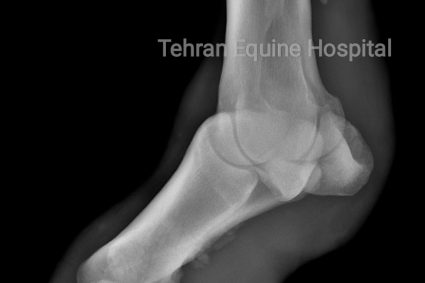

Pastern luxation There is smoothly marginated new bone on the palmaromedial aspect of the proximal phalanx at the region of insertion of the sesamoidean ligament.

Pastern Luxation